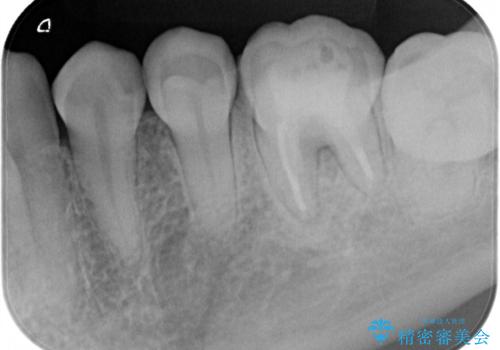

- 他院で自費根管治療、矯正治療、セラミック治療をする予定でしたが、根管治療終了後から忙しく通わなくなり放置していました。

海外転勤が決まったため、それまでに治療をしてほしいとご来院されました。(矯正治療はせずにセラミック治療のみ)

海外転勤が決まり、急いでセラミック治療をしてほしいとご来院された患者様です。

根管治療に症状がなく、上の歯に関しては土台もそのまま使用可能であったため、下の歯の土台、上下の歯のセラミック治療を行いました。